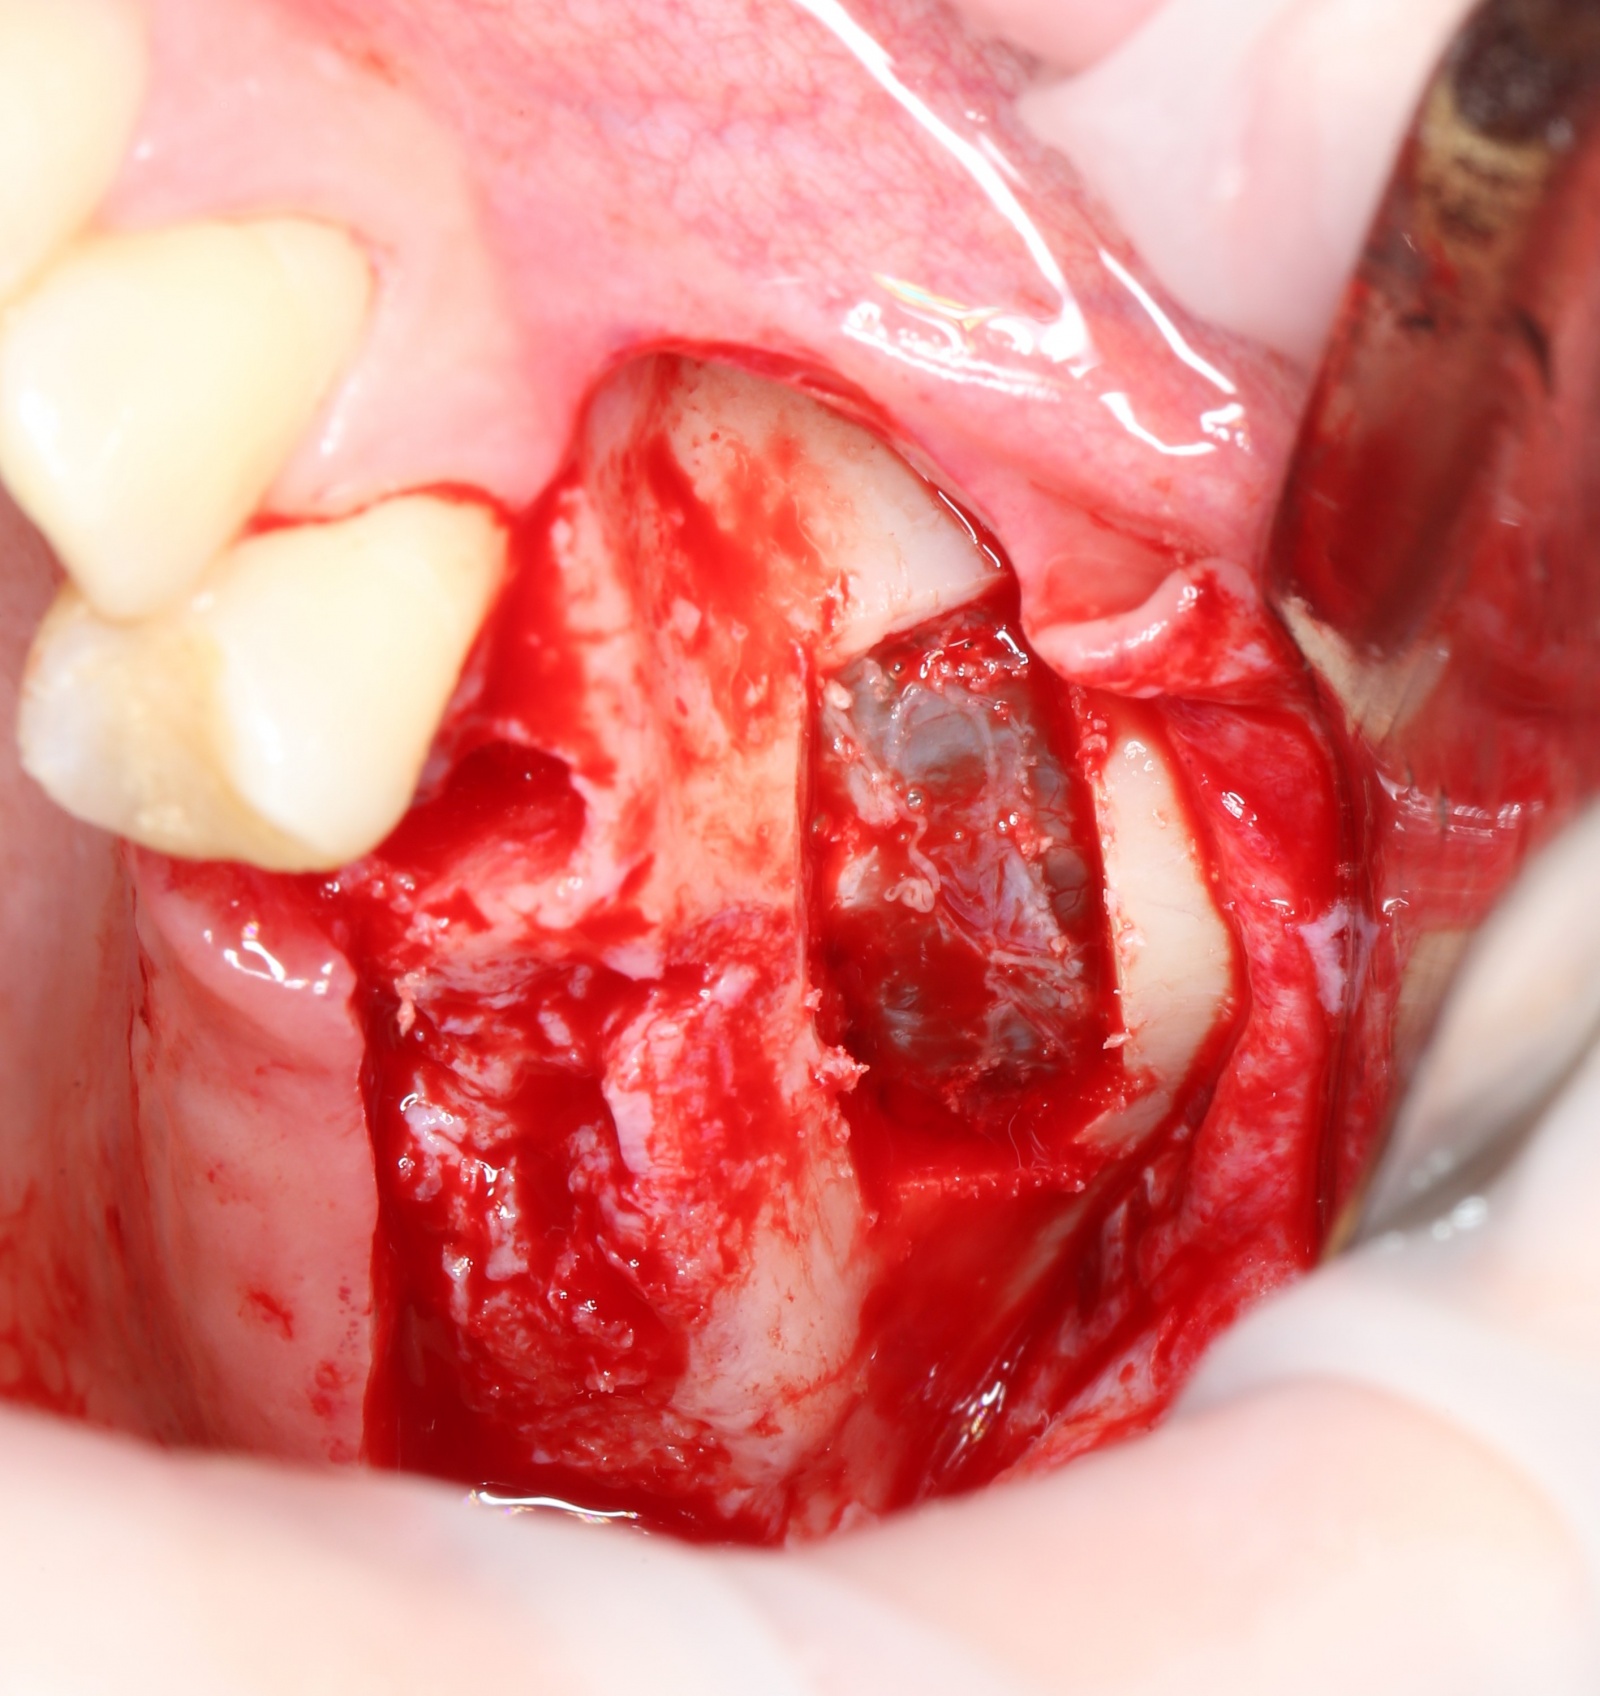

После того, как анестезия подействовала, при помощи скальпеля производится разрез, а распатора — скелетирование кости (отделение надкостницы от компактного вещества кости).

Разрез:

Скелетирование кости:

«Вжух»:

Лунка моментально заполняется кровяным сгустком.

Хорошо видно слизистую оболочку, которая выстилает пазуху изнутри: